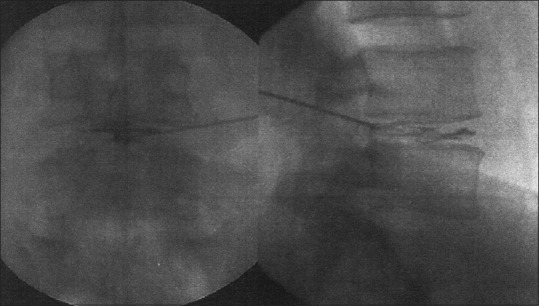

The skin entry point was about 12–14 cm from the midline, and the needle insertion was done. The needle is navigated into the disc space through the Kambin's triangle using the C-arm [Figure 1].

Figure 1.

Needle insertion technique: (At the medial pedicular line in the anteroposterior view and the posterior vertebral line in the lateral view on fluoroscopy)